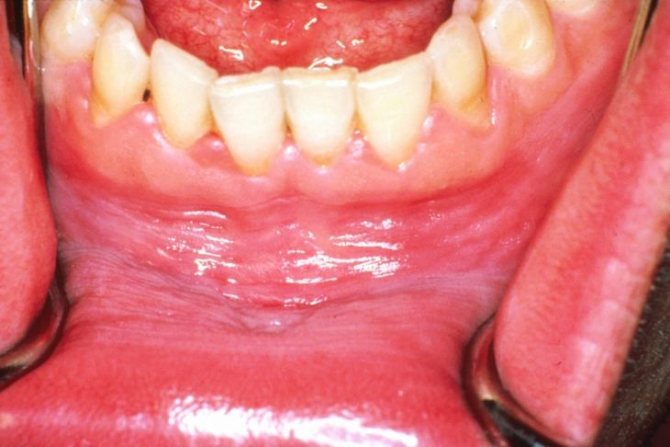

Фото: Волосатая лейкоплакия языка

Фото лейкоплакии